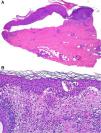

HistopathologyTwo skin biopsies were performed. The first showed a subepidermal blister with scant inflammatory content (Fig. 2A), and the second marked eosinophilic spongiosis (Fig. 2B).

Differential diagnosisDifferential diagnosis in the presence of postoperative blistering lesions includes bullous impetigo, which was ruled out by the negative culture, and allergic contact eczema, excluded based on patch testing. In case of a histological finding of a subepidermal blister with minimal inflammatory infiltrate, other considerations include the cell-poor variant of bullous pemphigoid, epidermolysis bullosa, porphyria cutanea tarda, burns (e.g., from cryotherapy), and even toxic epidermal necrolysis.1 The clinical picture, along with the second biopsy showing intense eosinophilic spongiosis, led us to the diagnosis of localized bullous pemphigoid,2 which was confirmed after detection of anti-basement membrane antibodies in the patient's serum.